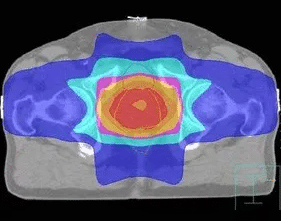

調(diào)強(qiáng)適形放射治療(IMRT)

以往放射治療使用的都是強(qiáng)度幾乎一致的射線,而腫瘤本身的厚度是不均一的,因此造成腫瘤內(nèi)部劑量分布不均。為了實(shí)現(xiàn)腫瘤內(nèi)部劑量均勻,必須對照射野內(nèi)的射線強(qiáng)度進(jìn)行調(diào)整。

IMRT技術(shù)要求把一束射線分解為幾百束細(xì)小的射線,分別調(diào)節(jié)每一束射線的強(qiáng)度,射線以一種在時(shí)間和空間上變化的復(fù)雜形式進(jìn)行照射。

IMRT通過改變靶區(qū)內(nèi)的射線強(qiáng)度,使靶區(qū)內(nèi)的任何一點(diǎn)都能得到理想均勻的劑量,同時(shí)將要害器官所受劑量限制在可耐受的范圍內(nèi),使緊鄰靶區(qū)的正常組織受量降到最低。

IMRT比常規(guī)放療多保護(hù)15% ~20%的正常組織,同時(shí)可增加20% ~ 40%的靶區(qū)腫瘤劑量。